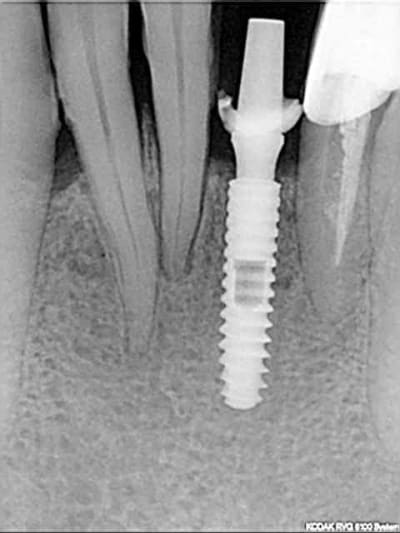

Ce n'est qu'un problème de réglage et comme je l'ai dit avec Leone le SAV et le controle ne me prennent que 10 MN en temps total. Cela fait 4 mois, il s'agissait de la rx juste après la pose de l'implant (extraction implantation)

Je l'ai utilisé il y a 5 ans sur une canine en potection totale (Pas le choix car en classe 2- 2).Depuis c'est la PM derrière qui a laché. Je te joins la RX.

Rx implant cad 2 cpyqbp - Eugenol

rx à j=0 et j+4 mois

ce qui est surprenant , c'est la présence d'os au niveau du col.

Oui on connait chez Leone mais reproductible sur toute la gamme. C'est qu"est que je dit! Mais nous c'est démontable et indexé. Un vieux cas en rx 5 ans entre les deux rx.